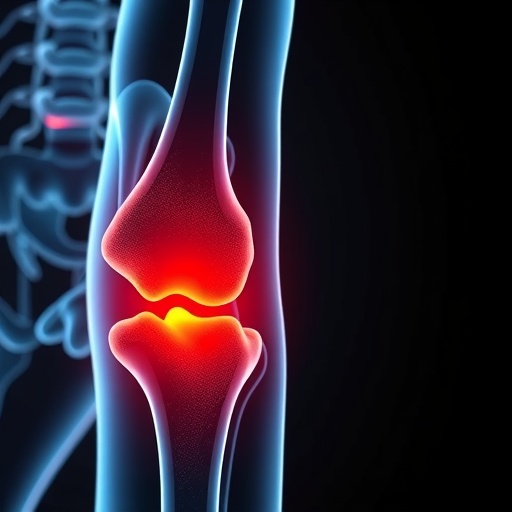

In a remarkable breakthrough that could redefine the therapeutic landscape for osteoarthritis (OA), researchers have identified the pivotal role of VGLL4 in maintaining extracellular matrix homeostasis in joint tissues. This discovery not only sheds light on the molecular underpinnings of OA but also opens promising new avenues for interventions that could halt or even reverse the debilitating progression of this chronic disease—a condition that currently affects hundreds of millions globally.

Osteoarthritis is characterized by the degeneration of articular cartilage and remodeling of the periarticular bone, culminating in pain, stiffness, and reduced mobility. Despite its prevalence, the molecular mechanisms orchestrating the interplay between cartilage degradation, extracellular matrix (ECM) disorganization, and joint inflammation have remained elusive. The study conducted by Suo et al. unveils that VGLL4, a transcriptional cofactor previously understudied in joint biology, serves as a critical guardian of ECM integrity.

Using a meticulous preclinical model mimicking human OA, the researchers employed sophisticated genetic and pharmacological tools to manipulate VGLL4 activity. Remarkably, enhancing VGLL4 expression forestalled ECM deterioration and remarkably mitigated hallmark features of osteoarthritis, including cartilage erosion and synovial inflammation. This strongly suggests that VGLL4 is not simply a passive marker but an active modulator capable of restoring and maintaining joint tissue quality.

This comprehensive study also employed state-of-the-art imaging and biomechanical assessments to validate the structural and functional integrity of treated joints. These quantitative approaches corroborated histological findings, confirming that VGLL4-centered interventions enhanced cartilage thickness, reduced osteophyte formation, and preserved biomechanical resilience.